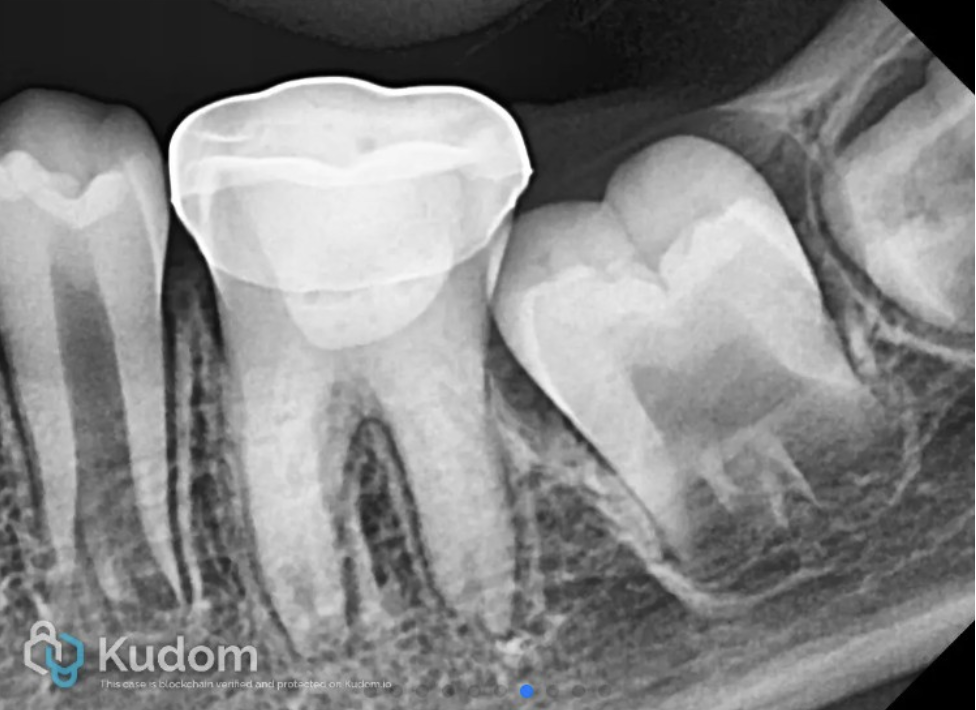

The patient received a stainless-steel crown at a follow-up appointment one week later. Periodic follow-up was done till 30 months.

IOPA after cementation of stainless steel crown

Fig. 5

Follow-up IOPA at 6 months

Fig. 6

Follow-up IOPA at 12 months

Fig. 7

Follow-up IOPA at 18 months

Fig. 8

Follow-up IOPA at 24 months

Fig. 9

Follow-up radiograph at 30 months showed resolution of periapical lesion, and completion of root formation and establishment of lamina dura.